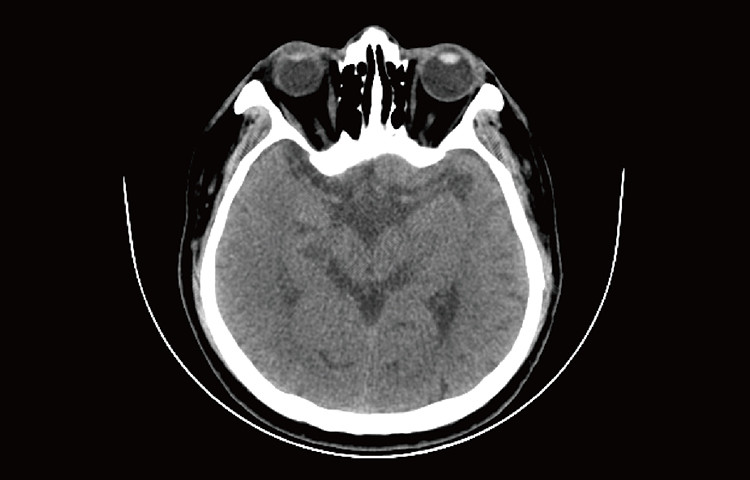

Скриншоты снимков